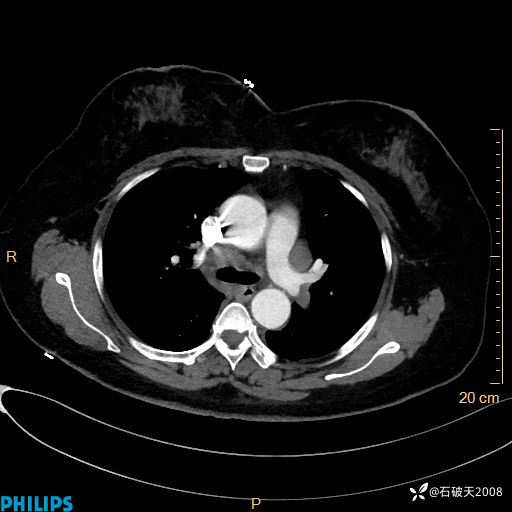

肺结节病?纵膈型肺癌?淋巴瘤?有点意思,欢迎围观

女 52岁 主 诉:咳嗽10余天,咳痰2天。

现病史:10余天前无明显诱因出现咳嗽,呈阵发性干咳,伴咽喉部发痒,无咽痛,无咳痰,无鼻塞、流涕、打喷嚏,无发热、畏寒、寒颤,无头痛、头晕,无胸闷、胸痛,无反酸、烧心,无腹痛、腹泻,无尿频、尿急,无皮疹等,在当地诊所求治,给予口服药物治疗(具体不详),病情无好转。遂在当地社区卫生服务中心开具口服药物治疗(具体不详),疗效欠佳。2天前出现咳痰,在我院门诊求治,行胸部CT提示肺部感染,建议住院,患者要求口服药物治疗,目前仍咳嗽、咳白色粘痰,白天量多,夜间自觉喉部喘鸣音,遂再次来院就诊,以“肺部感染”为诊断收入院。发病以来,神志清,精神可,饮食可,夜间睡眠差,大小便正常,近期体重无明显变化。

纵隔窗